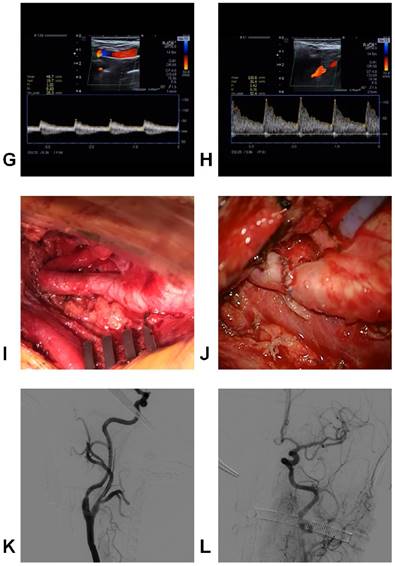

DICAs are not uncommon ICA diseases and can be classified by their tortuosity, coiling and kinking. Due to blood flow reduction, DICAs can result in symptoms of the brain and eyes due to insufficient blood supply. In addition, DICAs can be present with a pharyngeal bulge and pulsation. The diagnostic tools for DICAs include Doppler ultrasonography, CTA, MRA and DSA. Some DICAs, particularly those with symptomatic kinking, should be treated surgically, and the appropriate treatments for DICAs have their own surgical indications. Several methods, including correction of the bending of ICAs and shortening of ICAs, have been developed for the treatment of DICAs. The appropriate treatments for DICAs can result in good outcomes and are associated with low morbidity and mortality rates. However, despite the success of surgical reconstruction, an appropriate therapeutic treatment remains the subject of numerous debates due to the lack of multicentric, randomized and prospective studies. Here, we provide a typical case of DICA in which end-to-end anastomosis to shorten the ICA was performed. This case is shown in Figure 9.

Figure 9

Images of a typical case. A-B: MRI showed infarction of the right hemisphere, C: Perfusion MRI showed a reduction of cerebral blood flow in the right hemisphere, D-F: The CTA showed bilateral kinkings, and the right one was serious. G-H: The Doppler ultrasound showed that the proximal blood flow of the right ICA kinking was 48.7 cm/s, and the distal blood flow was 105.8 cm/s, I-J: The operation showed that the kinking was removed, and end-to-end anastomosis was performed to shorten the ICA. K-L: The intraoperative DSA showed that the ICA recovered its normal shape.